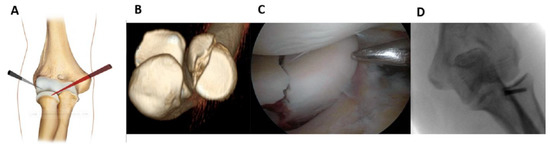

Fractures of the lateral half could be alternatively fixed by working posteriorly (working position PL) as described by Rolla et al. [16] (Figure 2).

Posterolateral and midlateral portals were created. From the superior view, the shaver and probe created the necessary space to reduce the fragment. The fixation technique was then completed by following the steps previously described.

Figure 2. Fracture of lateral half of radial head that is fixed using the posterolateral working position; posterolateral and midlateral portals were created (A). From the superior view, the shaver and probe created the necessary space to reduce the fragment. (B): Pre-operative x-ray showing the fracture. (C): Intraoperative image of fracture fixation. (D): Control x-ray.